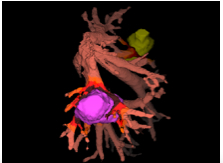

Risikoanalyse (vollautomatisch)

Eine vollautomtische Risikoanalyse berechnet nun den Abstand der Gefäße zu den Tumoren. Gefäße, die in der Nähe eines Tumors liegen werden farblich hervorgehoben. Hier muss bei der Resektion besonders vorsichtig agiert werden.